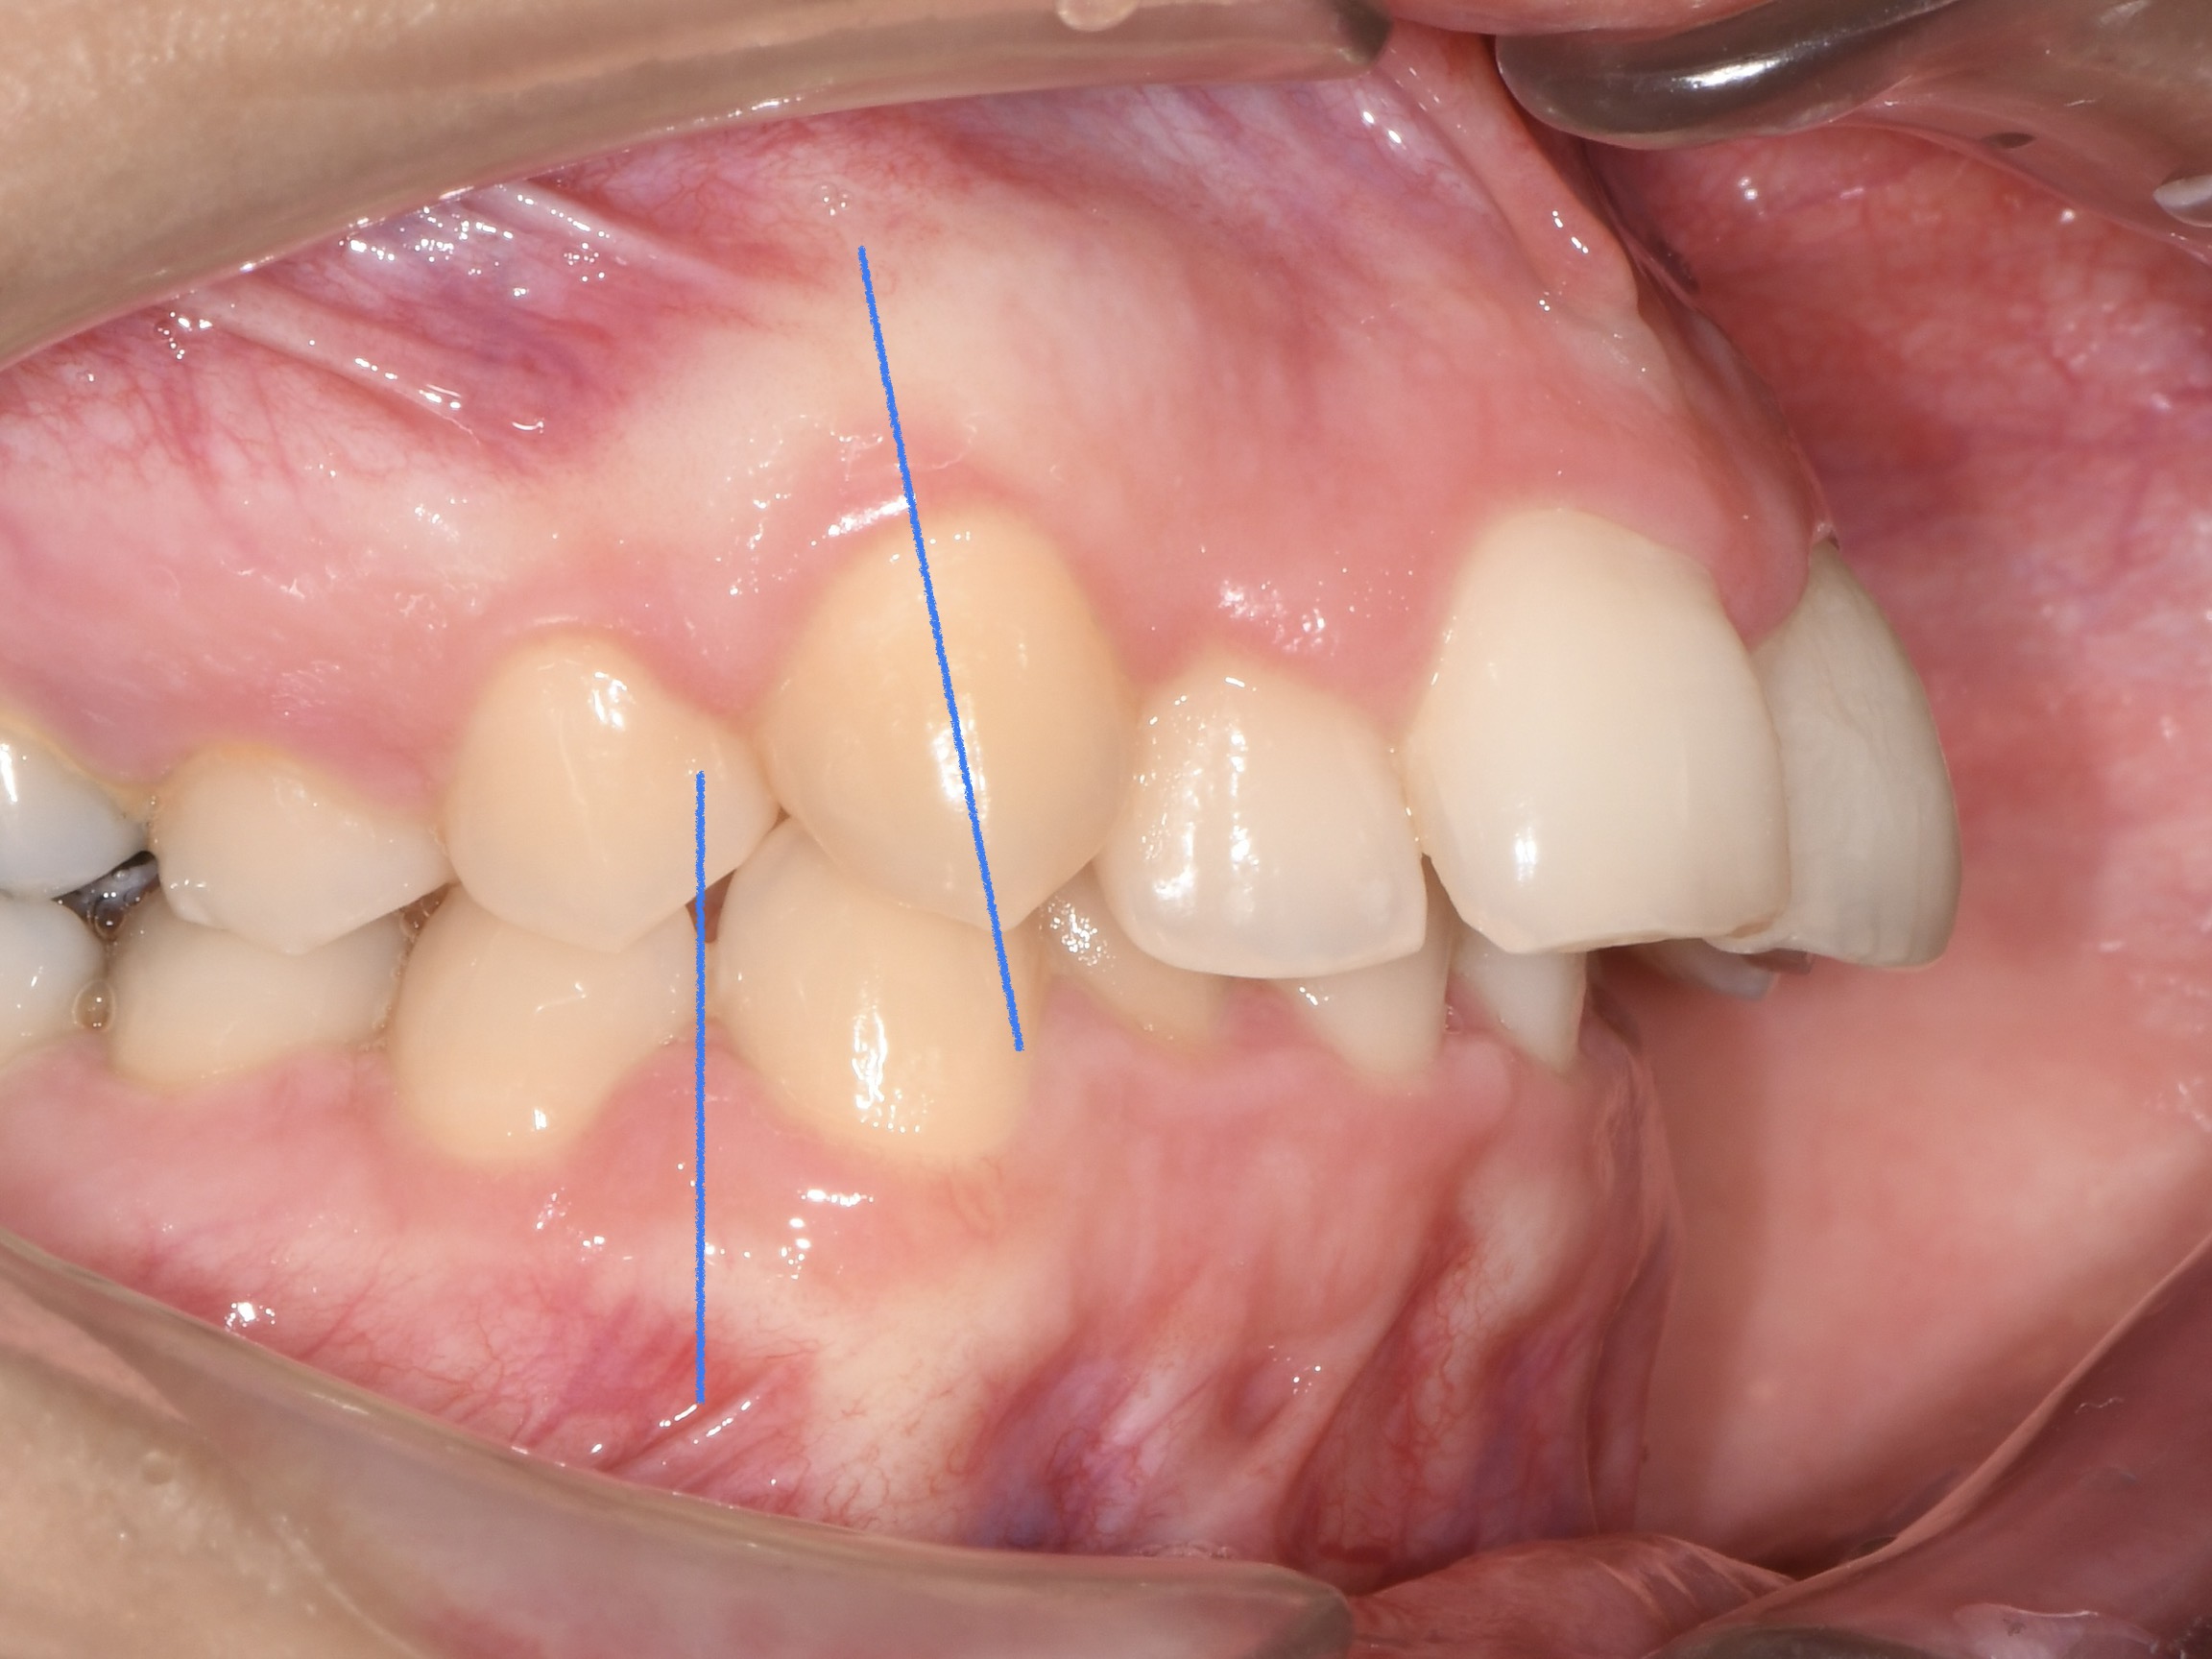

Az elmúlt évekből rengeteg szakmai referenciát tudnánk bemutatni, amelyek különböző fogszabályozási problémákat oldottak meg. Válogatva a több száz esetből, ezen az oldalon olyan képeket, információkat igyekeztünk bemutatni, amelyeknek a segítségével a jövőbeni pácienseinknek azt tudjuk üzenni: A Te fogsorod is lehet gyönyörű!

(Képeket a Pácienseink külön írásos beleegyezésével mutatjuk be!)